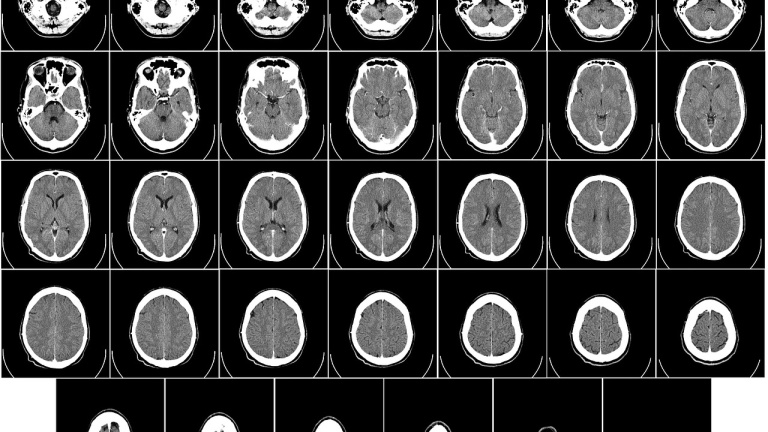

Un nuevo tratamiento experimental contra el cáncer de cabeza y de cuello puede ayudar en reducir los tumores en pacientes con enfermedad metastásica no curable, según informa The Guardian. El tratamiento consiste en una combinación de medicamentos que estimula el sistema inmunológico. El estudio se encuentra todavía en fase 3 y su valor estadístico es limitado.

El Instituto de Investigación de Cáncer británico presentó el estudio este año en el congreso de la Sociedad Europea de Medicina, donde explicaron que este tratamiento que sustituye a la quimioterapia fue probado en 947 pacientes con resultados increíbles. La terapia consiste en una mezcla de dos medicamentos, nivolumab y ipilimumab, las cuales provocan que el propio organismo sea el que ataque las células cancerígenas. Aquellos pacientes con altos niveles de PD-L1 mostraron mejores resultados puesto que esta molécula regula la inmunidad de las células y puede identificar las células cancerígenas.